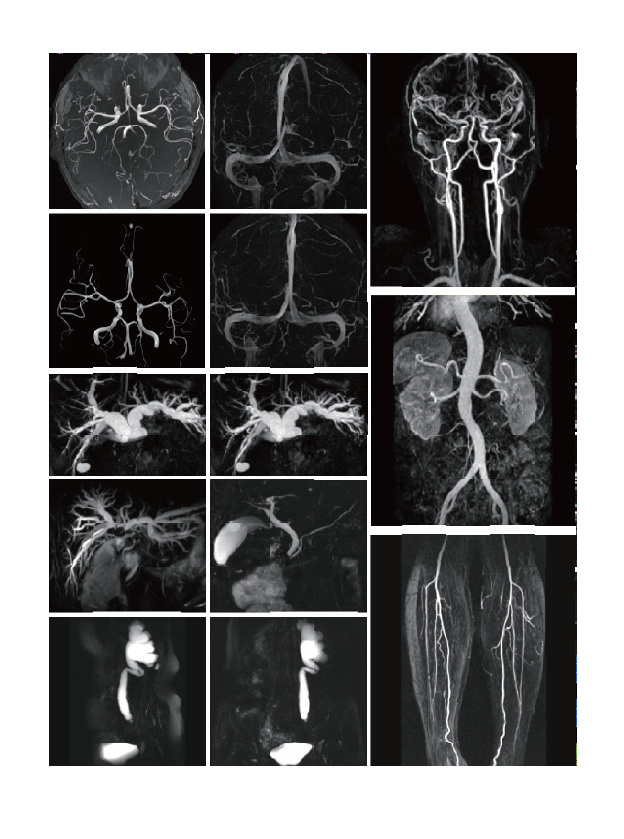

The examination range includes clinical applications such as nerves, blood vessels,abdomen, pelvic cavity, breast, tumor, orthopaedic limb joints, etc.

臨床畫廊